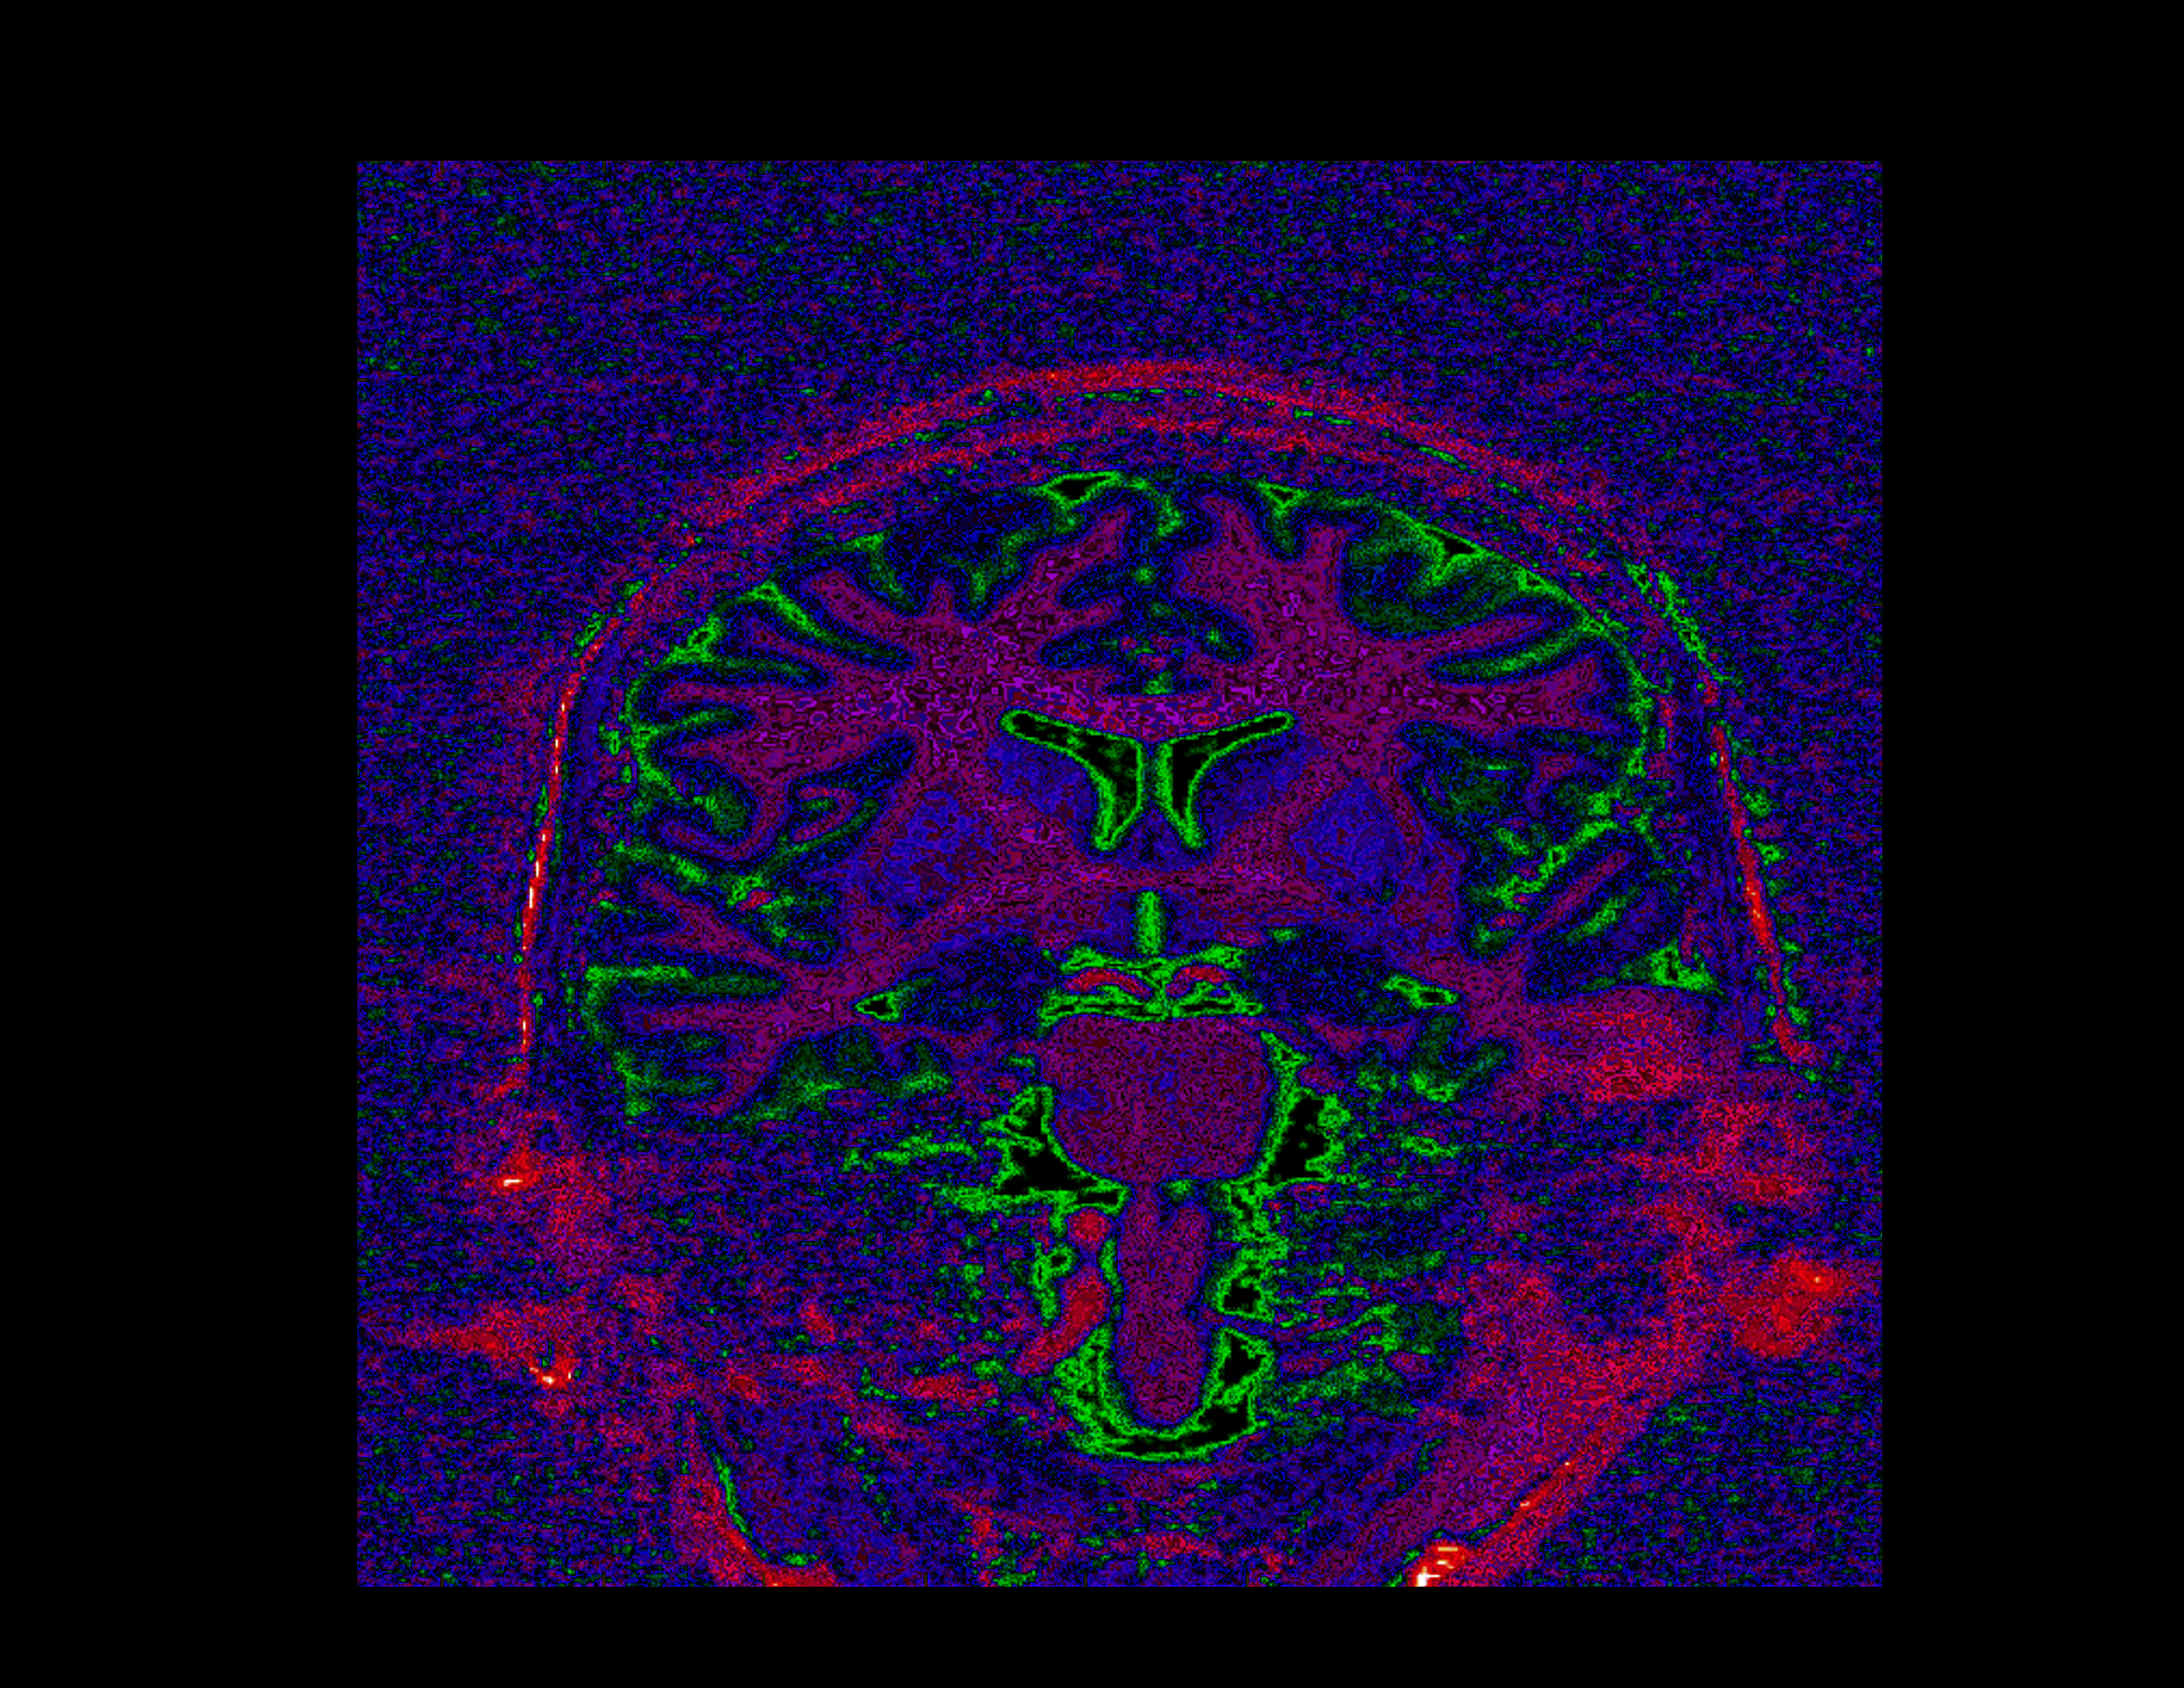

This coronol oblique slice is visualized with a semi-random color map, designed to highlight the subtle texture in the image.